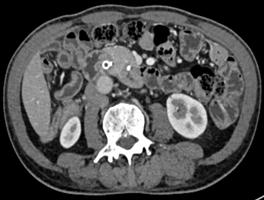

诊疗过程:患者高龄,一般情况差,手术风险高,患者及家属选择ERCP胆道支架植入及光动力治疗(不开刀、经自然腔道的微创手术,患者痛苦小)。ERCP术中因胆总管下段闭塞导丝不能进入胆总管,但是胰管插管成功,予以放置胰管支架(可改善胰管引流不畅,减轻胰管高压,改善消化功能);二期予以经皮经肝胆管穿刺(PTC)成功放置胆道支架(同样为微创,只需皮肤切开3mm的小口);待患者黄疸消退、全身情况改善后予以内镜下胆道肿瘤光动力消融术。术后多次复查腹部CT均提示胆总管下段肿瘤呈坏死的低密度灶,无复发征象。

术前提示肝内外胆管扩张,胆总管末端强化 | |

术后3月复查胆管下段病灶无强化,提示病灶无进展